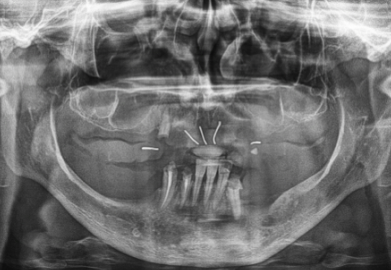

1. 초기 상담 및 진단

첫 방문 시 치과의사는 환자의 구강 상태를 평가하고, 임플란트가 적합한지 확인하기 위해 X-ray나 CT 촬영을 합니다. 이 과정은 일반적으로 한두 번의 방문으로 완료됩니다.